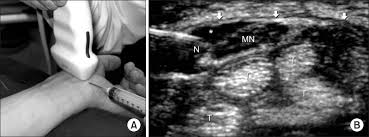

A Ultrasound Guided Carpal Tunnel Injection It Shows Transducer Download Scientific Diagram